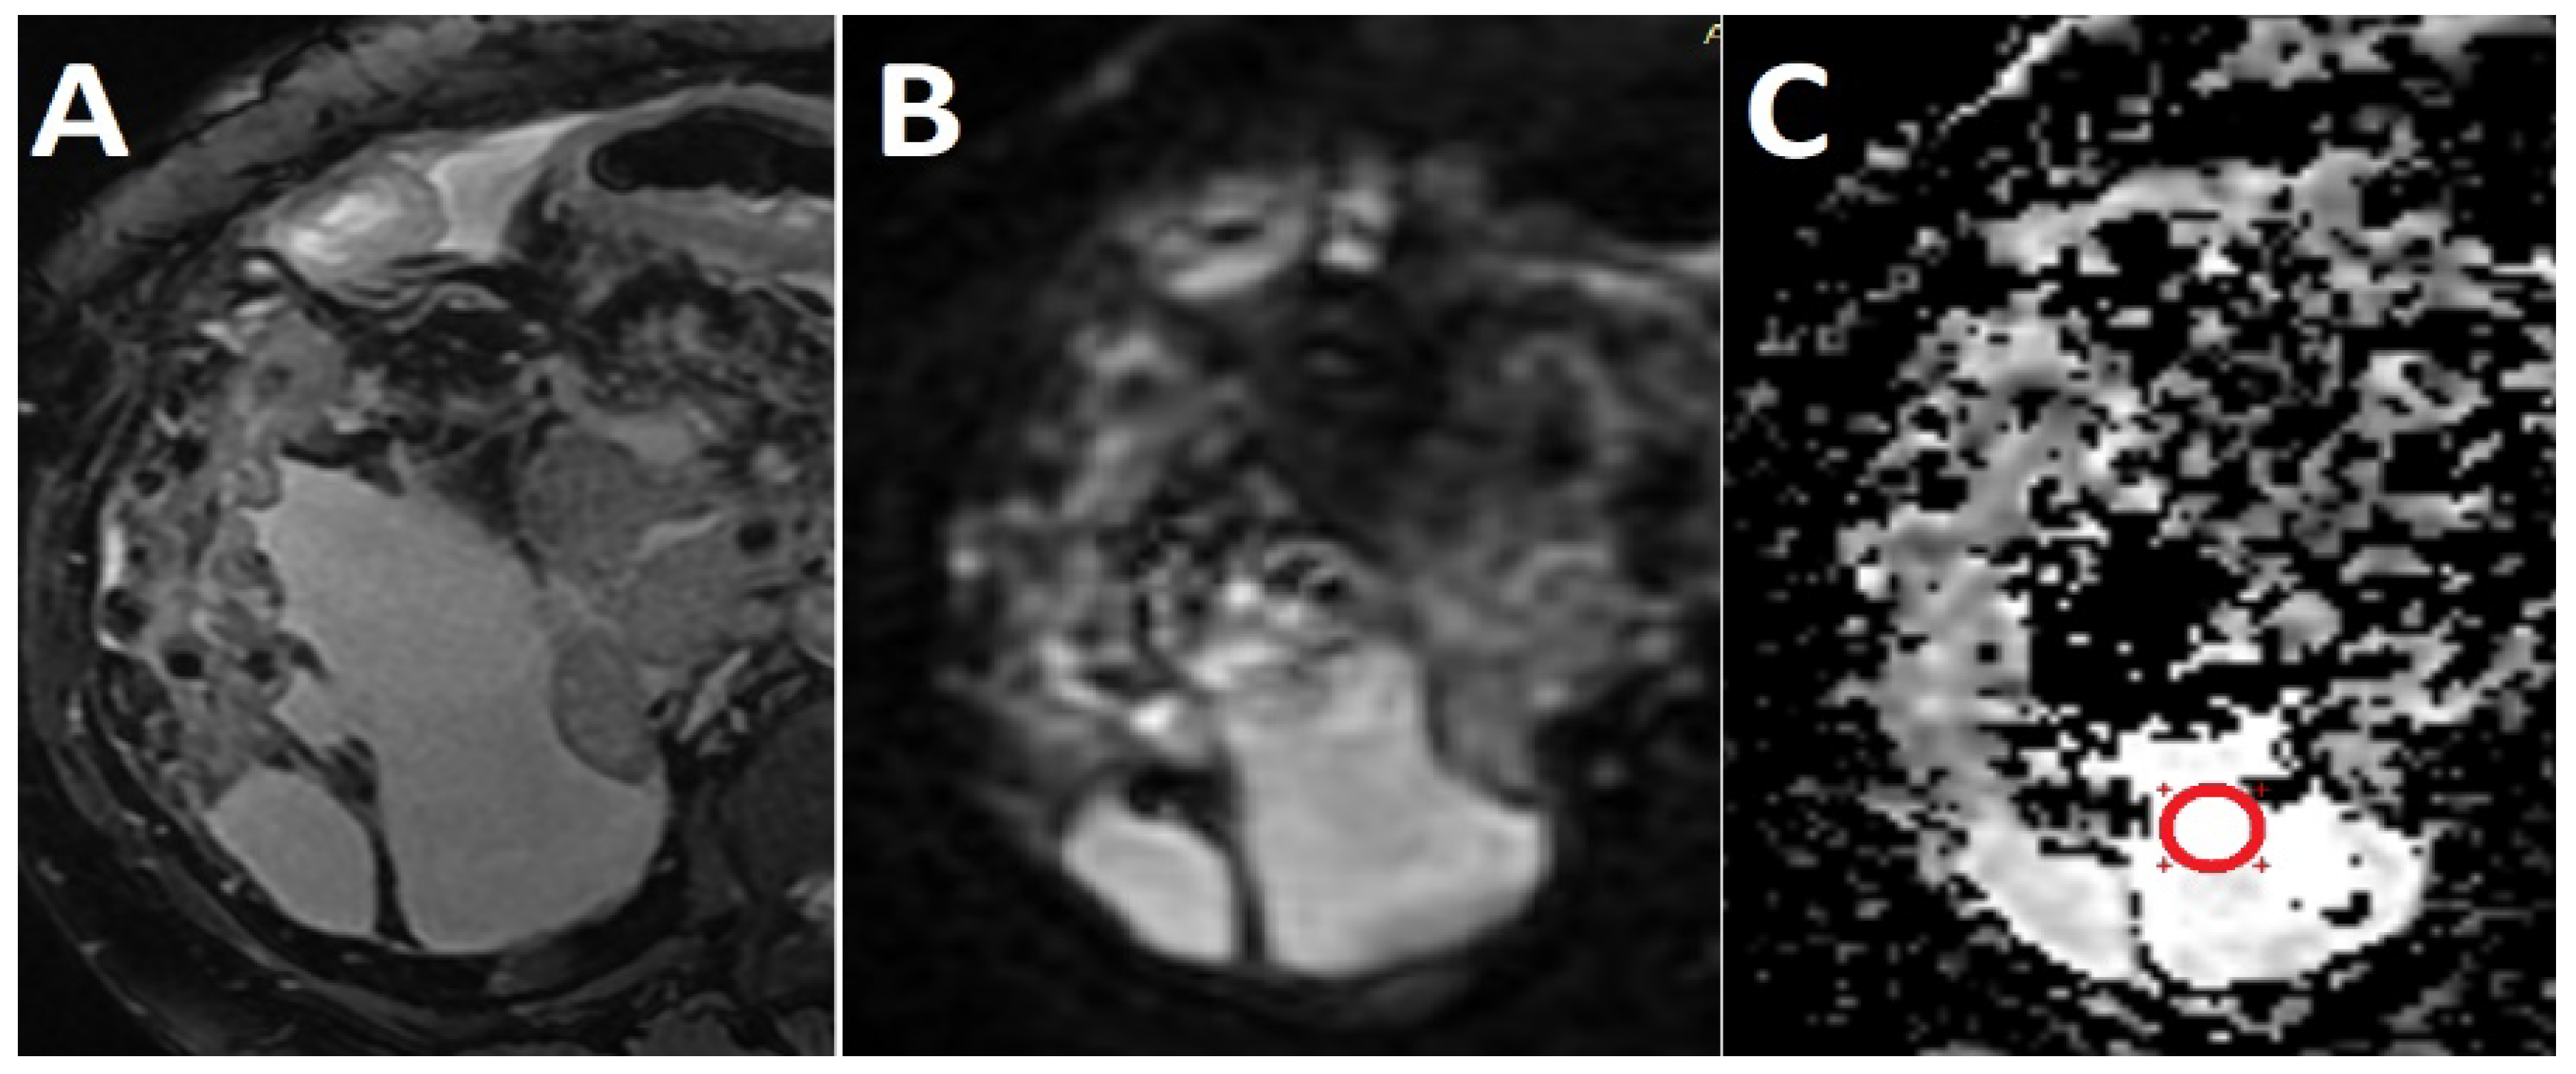

Diffusion-Weighted Magnetic Resonance Imaging as a Noninvasive Parameter for Differentiating Benign and Malignant Intraperitoneal Collections